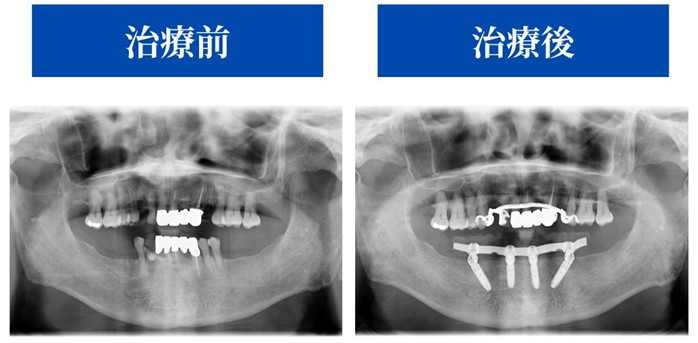

精密検査の結果、治療当日に仮歯が入るAll-on-4®︎治療を提案

CTなどによる精密検査の結果、

入れ歯に悩まれていた下の歯はAll-on-4®︎治療が可能と診断しました。

X-Guideを用いた「精度」を重視したインプラント治療

今回の治療でも、X-Guide(エックスガイド)という最先端ナビゲーションシステムを使用しました。

これは、オペ前のCTデータから立てたシミュレーション通りの位置・角度・深さでインプラントを埋入できるよう、リアルタイムでサポートしてくれるナビゲーションシステムです。

骨の量が限られている下顎の治療でも、安全な範囲を確保しながら、

理想的な角度で4本のインプラントを正確に埋入することができました。